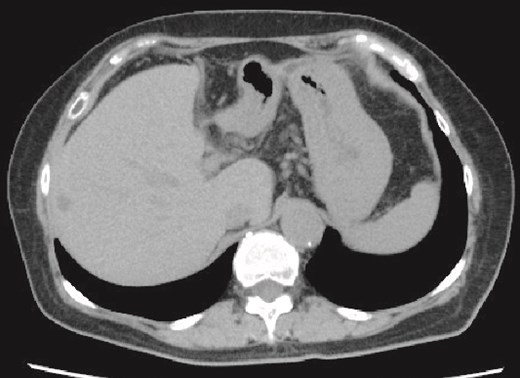

A 71-year-old female had suffered from upper abdominal pain for ~7–8 years. She consulted her primary care physician, and computed tomography (CT) demonstrated a 16-cm hepatic cyst in the left hepatic lobe (Fig. 1a). Although she had no history of peptic ulcer, she had not gotten an upper gastrointestinal endoscopy for decades.

(a) Enhanced CT images findings obtained in the examination by the patient’s primary care physician. A 16-cm hepatic cyst in the left hepatic lobe area was observed. Dotted line: The hepatic cyst. (b, c) Plain CT images findings obtained at the patient’s hospitalization. (b) This axial section shows the large hepatic cyst in left hepatic lobe area, which was collapsed and contained air bubbles. There were no findings of free air or leakage into the peritoneal cavity. Arrowheads: The air bubbles of collapsed large hepatic cyst. (c) A low-density area between the hepatic cyst and the duodenum with a suspicion of a fistulous tract can be seen on this coronal section. Arrows: The low-density area between the hepatic cyst and the duodenum. (d) An abdominal X-ray finding after the percutaneous catheter aspiration of the hepatic cyst with a 7Fr pig-tail catheter (left arrow). Right arrow: The nasogastric tube.

She exacerbated her upper abdominal pain and was transferred to our hospital. The laboratory workup (Supplementary Figs S1 and S2) showed that her white blood cell count and CRP level were high at 13 300/μl (92.5% neutrophil count) and 41.72 mg/dl, respectively. CT revealed a large hepatic cyst in the left hepatic lobe that was collapsed and contained air bubbles. There were no findings of free air or leakage into the peritoneal cavity (Fig. 1b). The CT also identified a low-density area between the hepatic cyst and the duodenum; a fistulous tract between them was suspected (Fig. 1c).